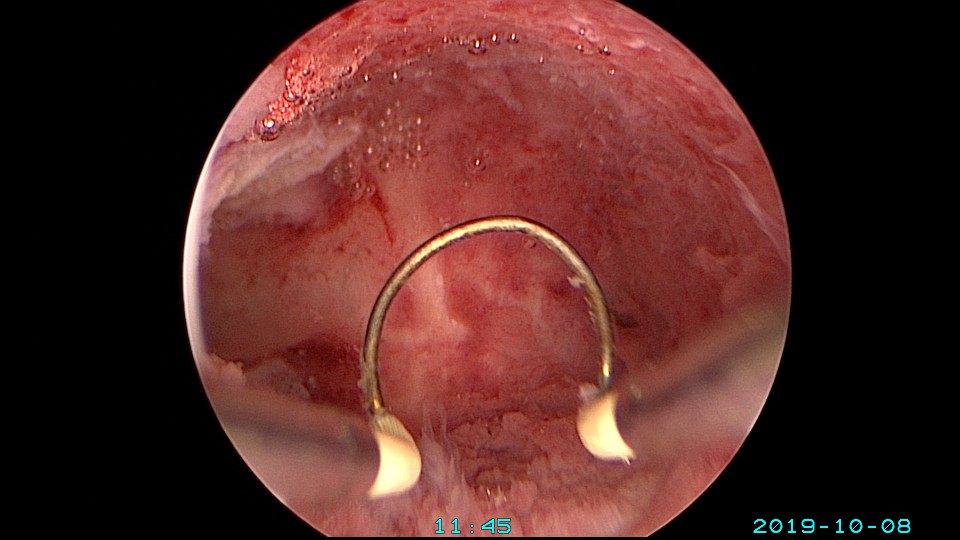

患者27岁,G2P0,人流1次,孕8周胎停清宫1次,绵阳市某医院造影发现宫腔粘连1+月,2019年10月初我院宫腔镜探查,发现宫腔右侧粘连,左侧输卵管开口可见,单极电切分粘,恢复宫腔形态,显露右侧输卵管开口。2019年10月底宫腔镜二探取球囊,宫腔形态正常,双侧输卵管开口可见。2021年10月自然妊娠,稽留流产,我院宫腔镜取胚,2022年再次自然妊娠,足月分泌。现33岁,G4P1。